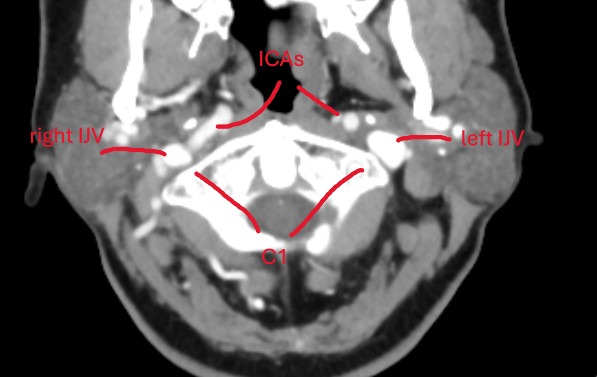

@chrEagle see attached annoted images (5 here of the axial view, and a 3D model in a following post)

Between the skull-base and C1, your left styloid comes in contact with your left IJV. Contact is normal, compression is not. I would be surprised if this contact is causing any symptoms.

Further down, at the level of C1, there is some compression of your left IJV against C1. Neither styloids are contributing to any compression here.

At the level of C2ish, your left IJV becomes compressed by your left ICA. Your ICAs are tortuous, in that they move from an anterior to posterior position and then go back to anterior position. On it’s way to to the posterior position, the left ICA compresses your left IJV.

There is no other IJV compression anywhere.